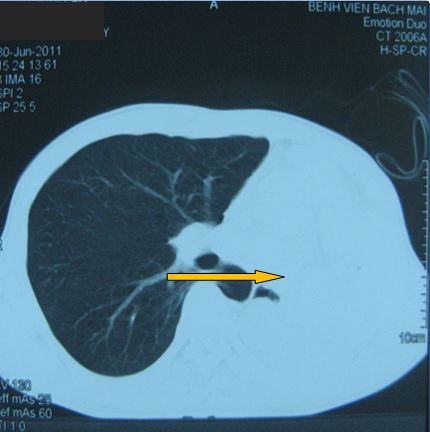

-          Bệnh nhân được tiến hành chụp cắt lớp vi tính ngực (CT ngực) đánh giá: có hình ảnh tổn thương toàn bộ thùy trên phổi trái

Hình ảnh tổn thương tái phát tương ứng với thùy trên phổi trái

Trước điều trị

Tổn thương ở vị trí thuỳ trên phổi trái: khối đông đặc và tổ chức u